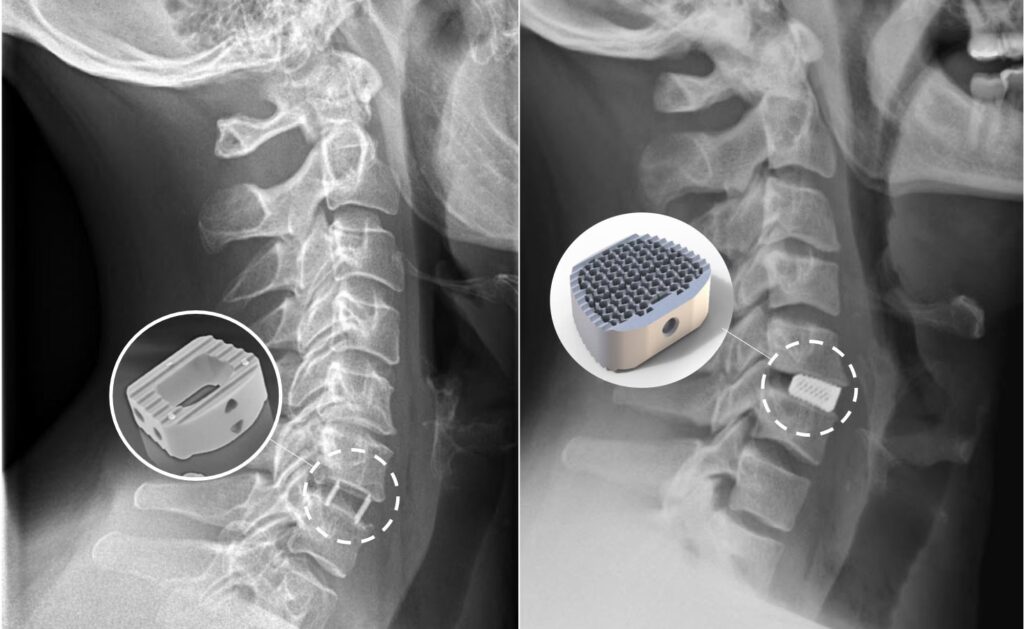

Den anden mulighed er at fjerne den beskadigede diskus og derefter forbinde de to tilstødende ryghvirvler, så de vokser sammen til én knogle. Dette kaldes en spondylodese eller en stivgørende operation. Kirurgen indsætter et lille bur (en 'cage') af metal eller plast i det tomme rum og fikserer ofte hvirvlerne med en lille metalplade og skruer. Med tiden vokser knoglerne sammen. Denne metode fjerner permanent bevægelsen i det opererede led. Selvom det lyder drastisk, har en stivgøring af et enkelt niveau i nakken ofte kun en minimal indvirkning på den samlede bevægelighed i hverdagen.